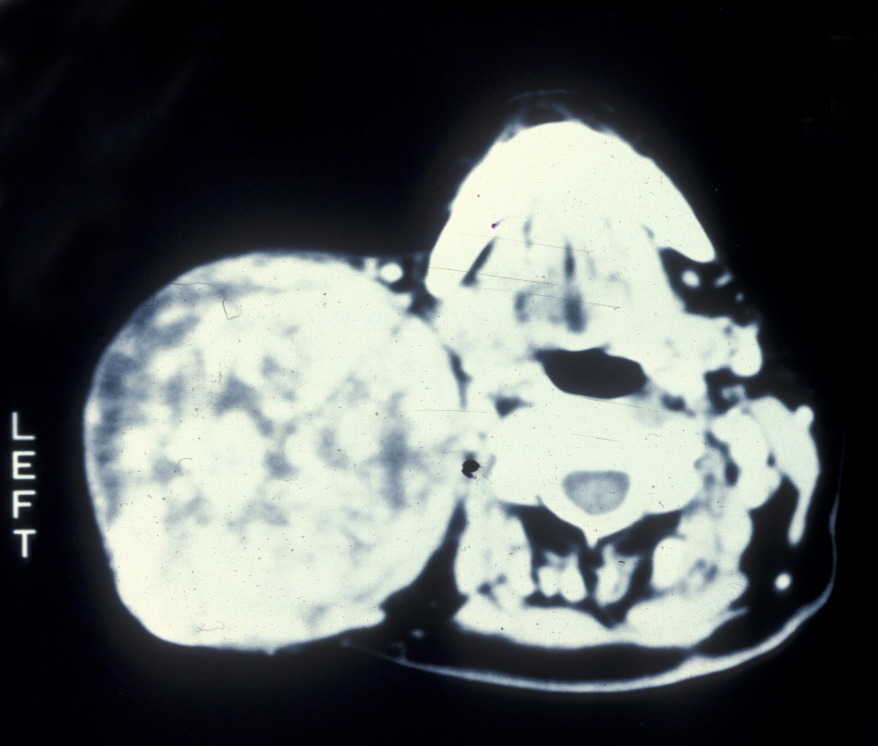

Presentation of virtually all these tumours is that of a slow growing mass (see Figure 8).

Figure 8: A CT scan showing a massive pleomorphic adenoma of the parotid gland.

The majority of salivary gland tumours are benign, malignant tumours of the salivary glands are very rare.

Pleomorphic salivary adenoma is the most common (benign) tumour of the salivary glands, 75 % of pleomorphic salivary adenomas occur in the parotid gland and the vast majority of those are in the superficial lobe. These tumours are thought to arise from duct and myoepithelial cells. They occur in equal proportion in men and women. The average age of presentation is around 40 years but they may present over a wide age range. The pleomorphic epithet (characteristic) arises from the mixed fibrous, myxoid, cartilaginous and epithelial components. Although benign, the pleomorphic salivary adenoma is poorly encapsulated and requires excision with a small margin of normal tissue.